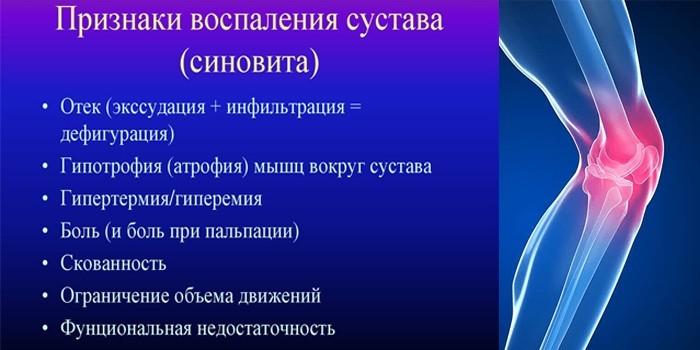

Заболевания и медицинские снимки: Жидкость в коленной чашечке

Раздел: Галерея прозрений